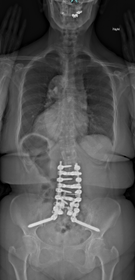

典型的な思春期特発性側弯症遺残変形・進行に伴う変性後側弯症・成人脊柱変形の患者さんです。正面・側面のバランスは破綻していて、難治性腰痛・脊柱管狭窄由来の下肢神経痛のためほぼ寝たきりとなっていました。

通常通り侵襲を軽減する目的で腰椎側方経路椎体間固定術、後方矯正固定術を2回に分けて行いました。正面・側面のバランスは良好で生理的な腰仙椎・体幹のshapeが獲得されています。腰痛、下肢神経痛は皆無となり、適度の散歩など穏やかな日常生活がおくれるようになりました。